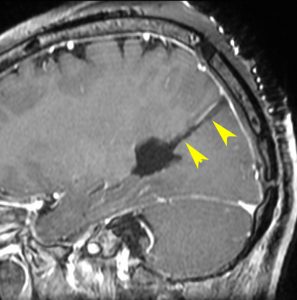

若い女性に偶然発見されたものです。直静脈洞と静脈洞交会の接合部あたりに発生したもので,静脈洞はほぼ閉塞に近い所見でした。しかし,この部分の静脈洞は,テント硬静脈側副路が発達することがあるので,硬膜を含めた積極的な摘出をすることは絶対にできません。もしほんの少しでも流れがある直静脈洞を閉塞させると短時間に脳死になるような脳静脈圧亢進が生じる可能性があるからです。静脈洞内に少し取り残して(右下の矢印)手術を終了しました。手術後には定位放射線治療を行って再増大を防ぎます,